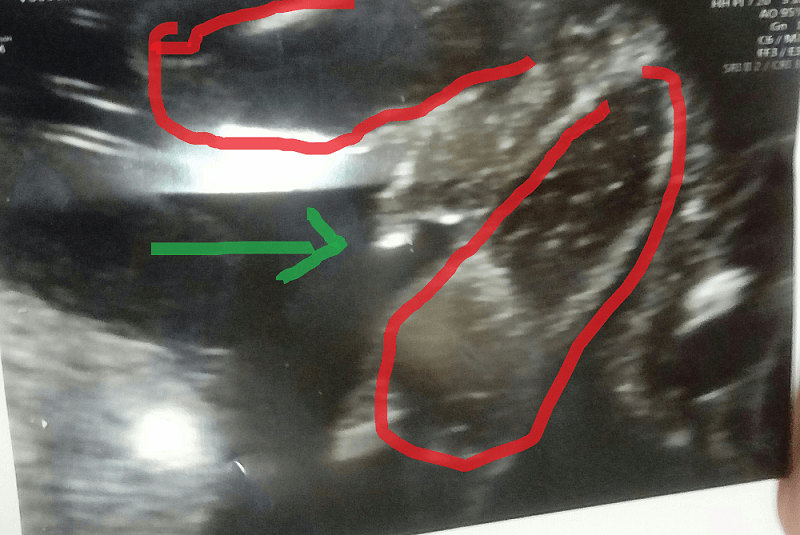

Jak dla mnie to widać, że chlopczykStrzałka przyrodzenie, czerwonym nogi oznaczyłam. Marta u Ciebie to i ja nawet widzę, ze chłopczyk... U mnie taka pewna nie jestem, ale to może przez to, że długo na dziewczynkę byłam nastawiona i moja psychika odrzuca myśl o chłopcu czy coś w tym stylu. Chociaż chłopiec też będzie cieszył, wiadomo.Zobacz załącznik 842408